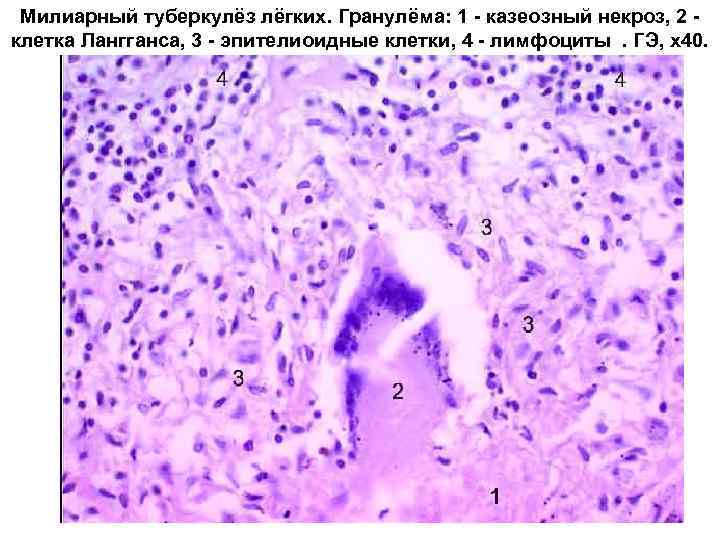

Микроскопический взгляд на мишитарный туберкулез легкого: фотодокументация

Раздел: Снимки-откровения